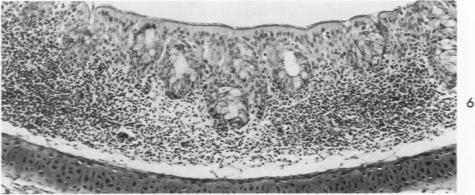

Acute Newcastle disease virus infection following intranasal inoculation of chicks with a mesogenic strain of the virus produced a localized infection of the middle turbinate which was histologically demonstrable 18 hours after inoculation. There was destruction of mucous cells of individual acini in the under surface of the middle turbinate, and the infection rapidly spread to ciliated and goblet cells and to neighboring acini. By day 2 there was simultaneous remodeling of the mucosa, continued destruction and inflammatory infiltration and frequent loss of cartilage basophilia. By day 3 polymorphonuclear cells almost disappeared, epithelial mitoses commenced, and lymphocyte infiltration intensified; the plasma cells normally present along the lateral nasal gland ducts were often destroyed, very occasionally the glands themselves were destroyed. By days 5 and 6 inflammation greatly decreased, and by day 8 the mucociliated epithelium was essentially normal. The infection is sequentially comparable to acute mild rhinitis of man.

用新城疫病毒的中等毒力株经鼻腔接种雏鸡后,会引发急性感染,在接种后18小时可通过组织学方法证实中鼻甲出现局部感染。中鼻甲下表面单个腺泡的黏液细胞遭到破坏,感染迅速蔓延至纤毛细胞、杯状细胞及相邻腺泡。到第2天,黏膜同时发生重塑,破坏和炎性浸润持续存在,软骨嗜碱性常常丧失。到第3天,多形核细胞几乎消失,上皮细胞开始有丝分裂,淋巴细胞浸润加剧;沿鼻外侧腺管通常存在的浆细胞常被破坏,腺管本身偶尔也会被破坏。到第5天和第6天,炎症大为减轻,到第8天,黏液纤毛上皮基本恢复正常。这种感染过程与人的急性轻度鼻炎有相似之处。